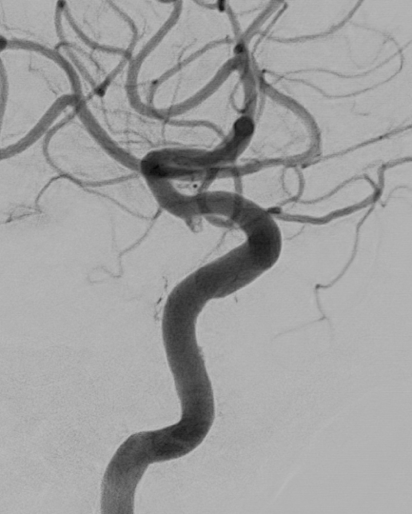

【MRA】

MRAでは左中大脳動脈が閉塞しているが、MRI,CTでの梗塞部位は血管支配領域すべてではなく、まだら状に出現。